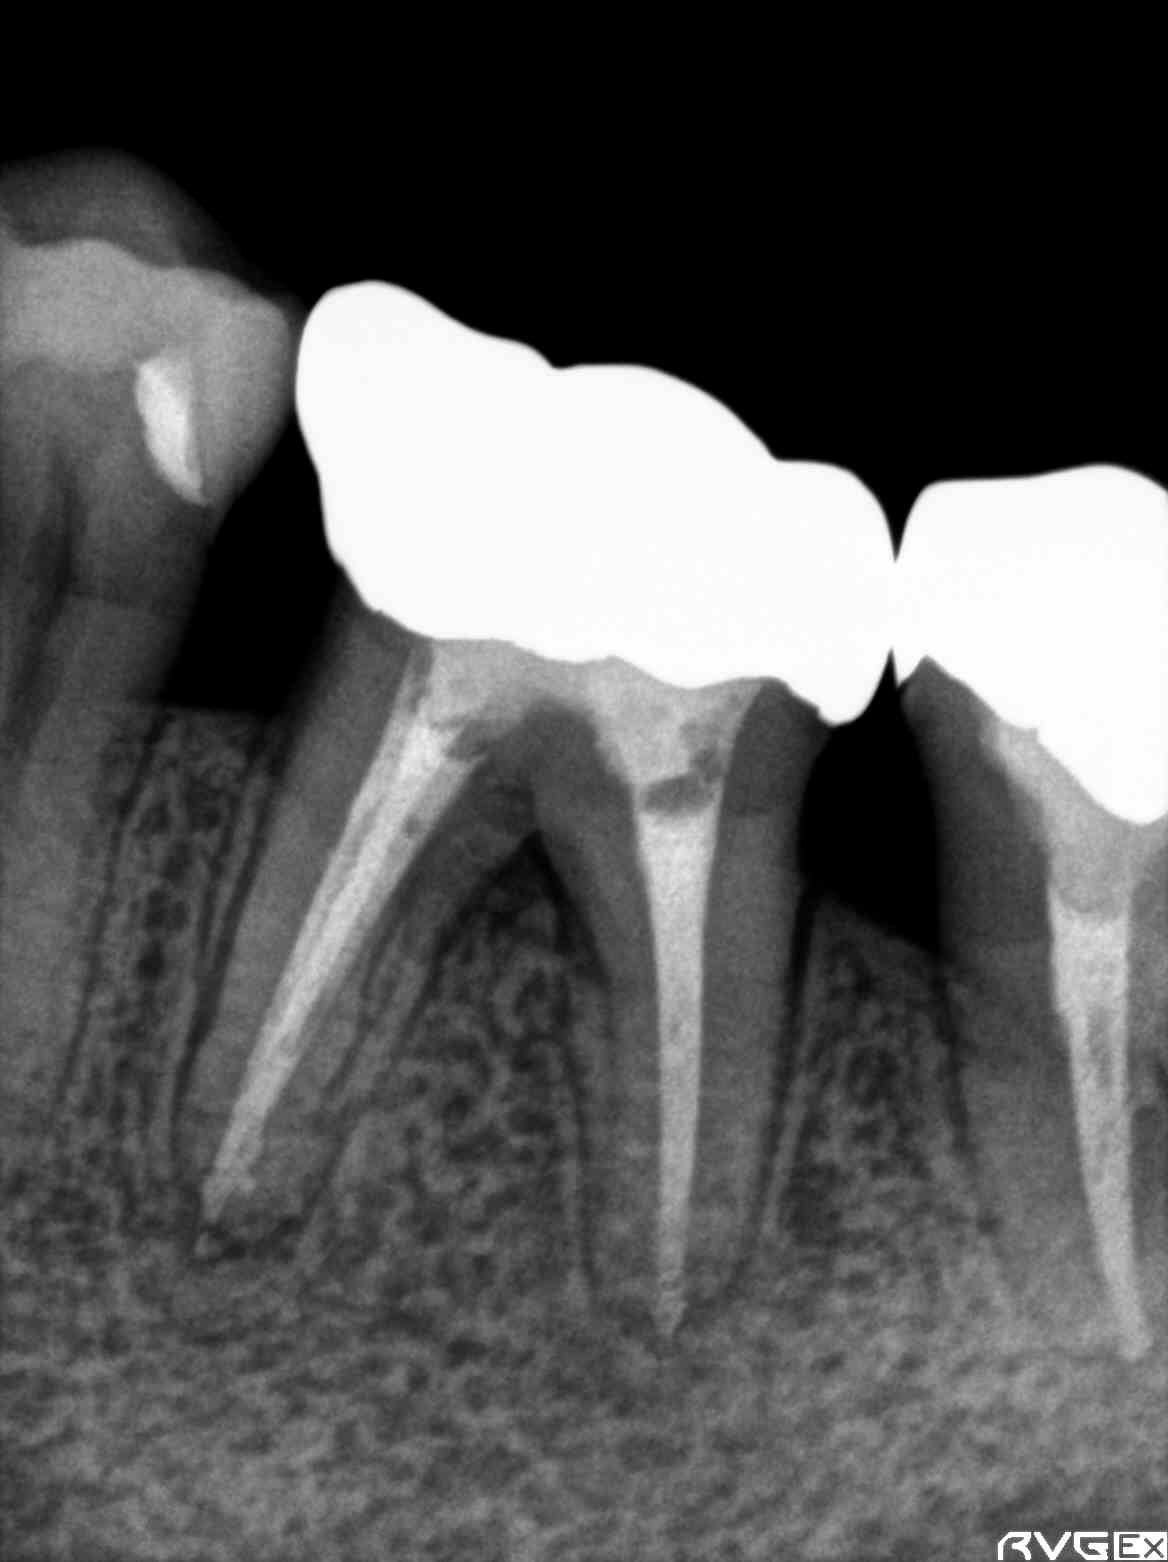

« Previous Post MTA(mineral trioxide aggregate)凄さ!